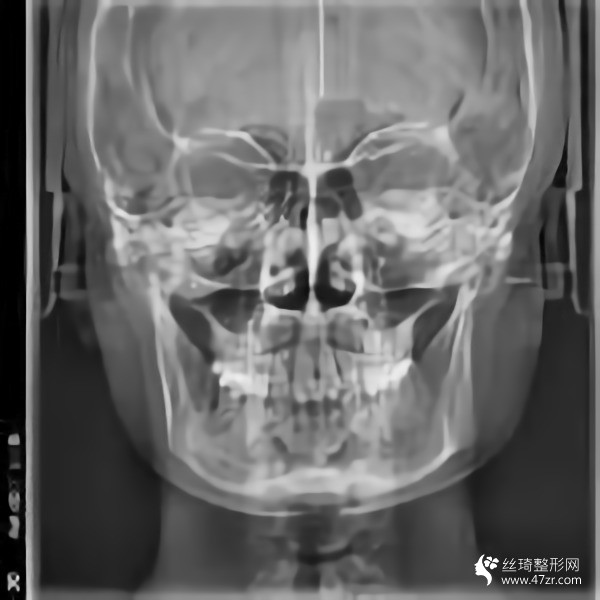

金柱翰院長韓國頜面整形專家、韓國鼻整形專家、下頜角截骨術技術專家、韓國“微整形技術研究”專家,多次接受記者采訪,南京醫(yī)科大學國際整形教學研究中心副主任,南京醫(yī)科大學友誼整形醫(yī)院專家委員會常委;擅長鼻整形手術:自體鼻中隔軟骨移植隆鼻,耳軟骨移植隆鼻,肋骨移植隆鼻,假體隆鼻,鼻尖鼻翼整形手術,各種畸形鼻的矯正,隆鼻失敗的修復,歪鼻的矯正;

從高中開始,人們就一直說我的臉很方。就算不直接說臉,我也會說臉很大。每次聽到心里都很無奈,臉上都在埋怨我...每次我回嘴的時候,也是一副滿不在乎的表情。然而,我的心還是不自覺地開始關心它。說白了,我要小一點的臉。其實我一直有做下頜角的想法。之前我還在讀書,沒錢。現在出來工作了,經濟獨立了,咨詢了醫(yī)院說可以,終于可以解決這個大面子問題了

手術后15天。過來拆線。反正我覺得我更喜歡自己。一點都好看??雌饋砗芸蓯邸D壳坝悬c腫,但輪廓線條開始慢慢顯現。畢竟拆線?;謴蜖顟B(tài)還是很滿意的。目前較重要的是照顧好自己。父母不在身邊。我還沒有過恢復期。我不能吃得太隨便。我必須注意我的飲食。這個真的是先苦后甜。不過為了后面的恢復果,一切都是值得的

回來快一個月了,基本沒有腫脹,輪廓清晰柔和。不知道是不是錯覺,感覺皮膚細膩多了。哈哈,雖然有美顏加持,但是大家看不出來很正常,但是可以自己感受一下。院長的技術真的很好,不愧是變臉王。剛來的時候看到幾個美女好像是花錢磨骨頭的,表現的多火啊。合格的醫(yī)生就是不一樣,讓人安心。醫(yī)院里的人手術后一直在回來康復。說起來有點太熱情了,讓我不敢接電話。

我又來了。我不記得上次是多久了。年紀大了記憶力下降了很多,但身邊認識的很多人也會這樣。好像沒有明X的辦法。再說說我的下頜角手術。雖然手術的時候感覺不深,但是手術后確實記得很深,總是需要經歷一些徹骨的寒冷,梅花才會有香味。較近的照片給你們發(fā)一波,如果手術做的好那么你以后就不會后悔了。

在生活中,我們往往忘記了健康和鍛煉,大多數人會在自己的世界里沉默,但生活中的許多實際問題仍然會把你拉回現實。我其實很喜歡去健身房,但是是時間問題導致我沒能得到我想要的。另外,我在下頜角休息了很久,臉部好了很多,運動還是不可或缺的。其實我覺得健康較重要,其次是外表和對自己的信任,哈哈